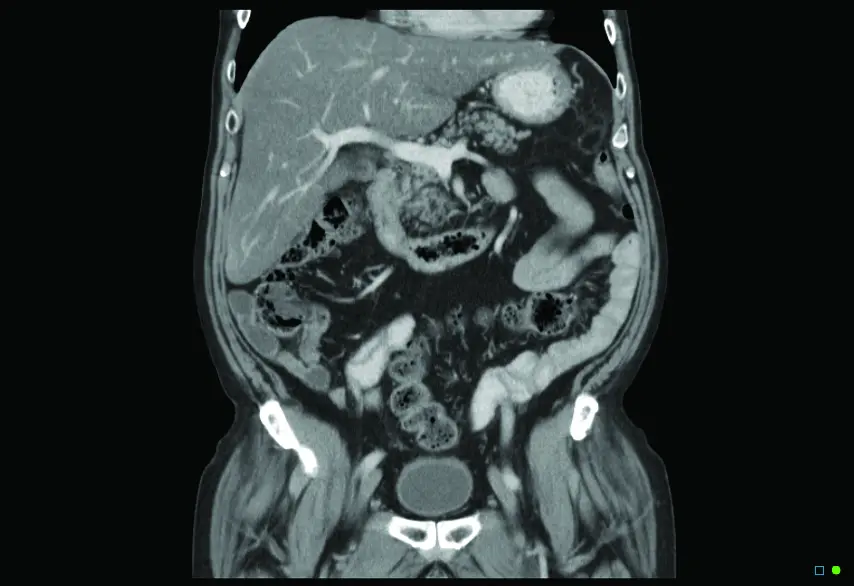

A CT (Computed Tomography) scan is an advanced imaging technique which uses X-rays to produce detailed cross-sectional images of your body. CT scans show the internal organs much better than standard X-rays do. They are a common and important examination technique in modern medicine.

Chest Abdo Pelvis CT 0001